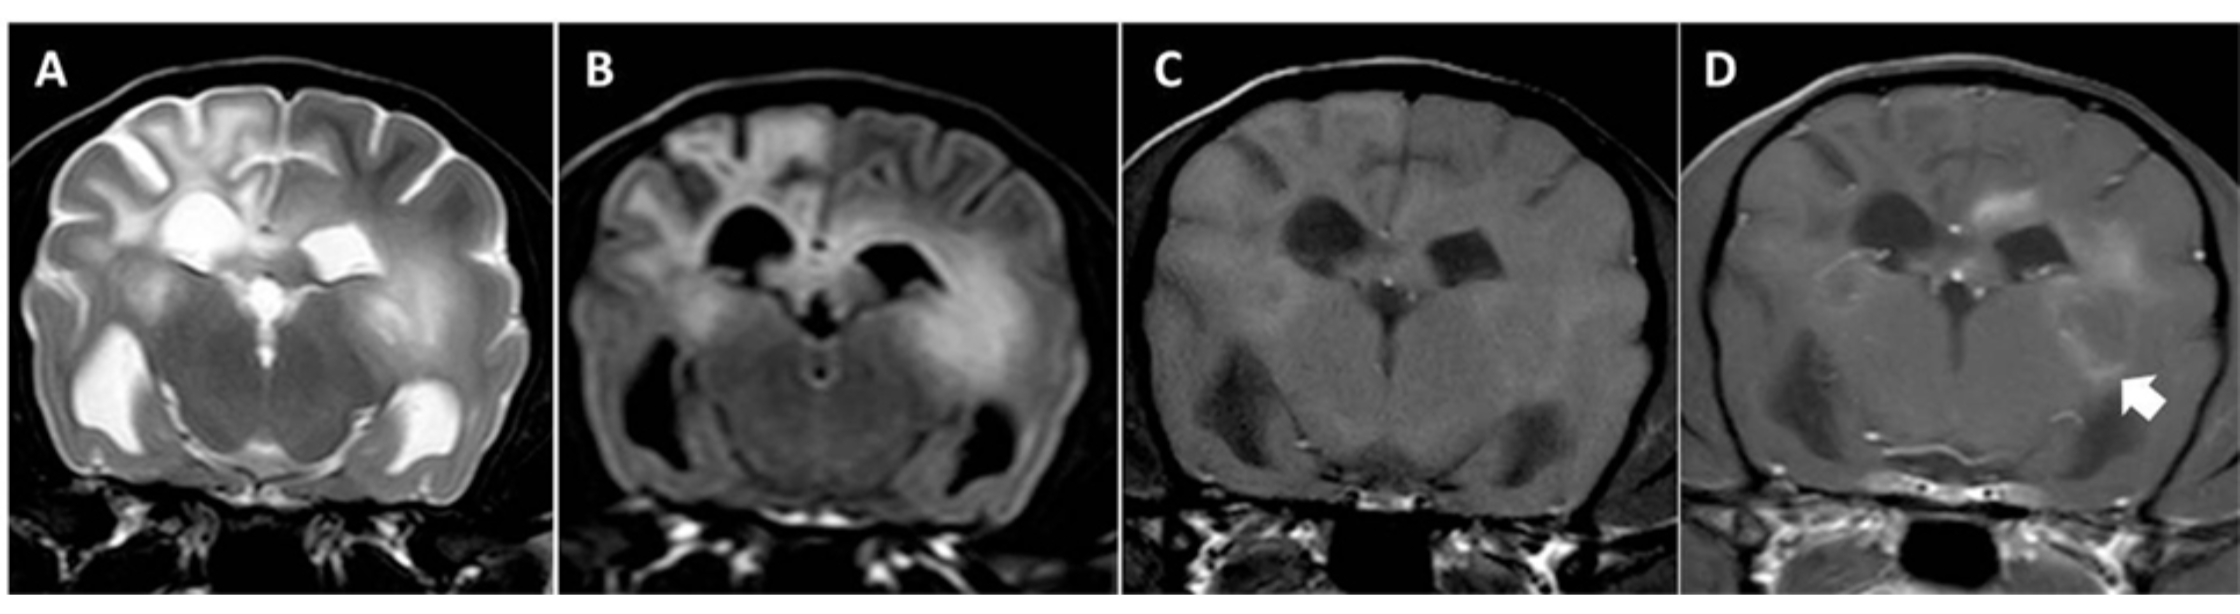

Inflammatory brain disease can look frightening from the outside, but advanced imaging gives a clear diagnosis and opens the door to targeted, highly effective treatment. Source: Encephalitis – Veterinary Neurology

Encephalitis (Inflammatory Brain Disease)

Inflammation within the brain, frequently immune-mediated. Early diagnosis is especially important because many cases respond well to medical therapy.

MRI for Brain Disease

MRI is the most sensitive and detailed imaging method for evaluating the brain and is considered the gold standard for diagnosing neurologic disease in dogs. It provides exceptional soft-tissue contrast, allowing veterinarians to see changes that cannot be detected with any other modality.

MRI is best for identifying:

• Brain tumors, including their exact size and location

• Inflammation such as encephalitis or meningitis

• Structural abnormalities affecting normal brain development or function

• Hemorrhage and vascular events in the brain

• Edema (swelling) and surrounding tissue changes

This level of detail allows for a precise diagnosis, accurate prognosis, and a treatment plan tailored to the specific disease.